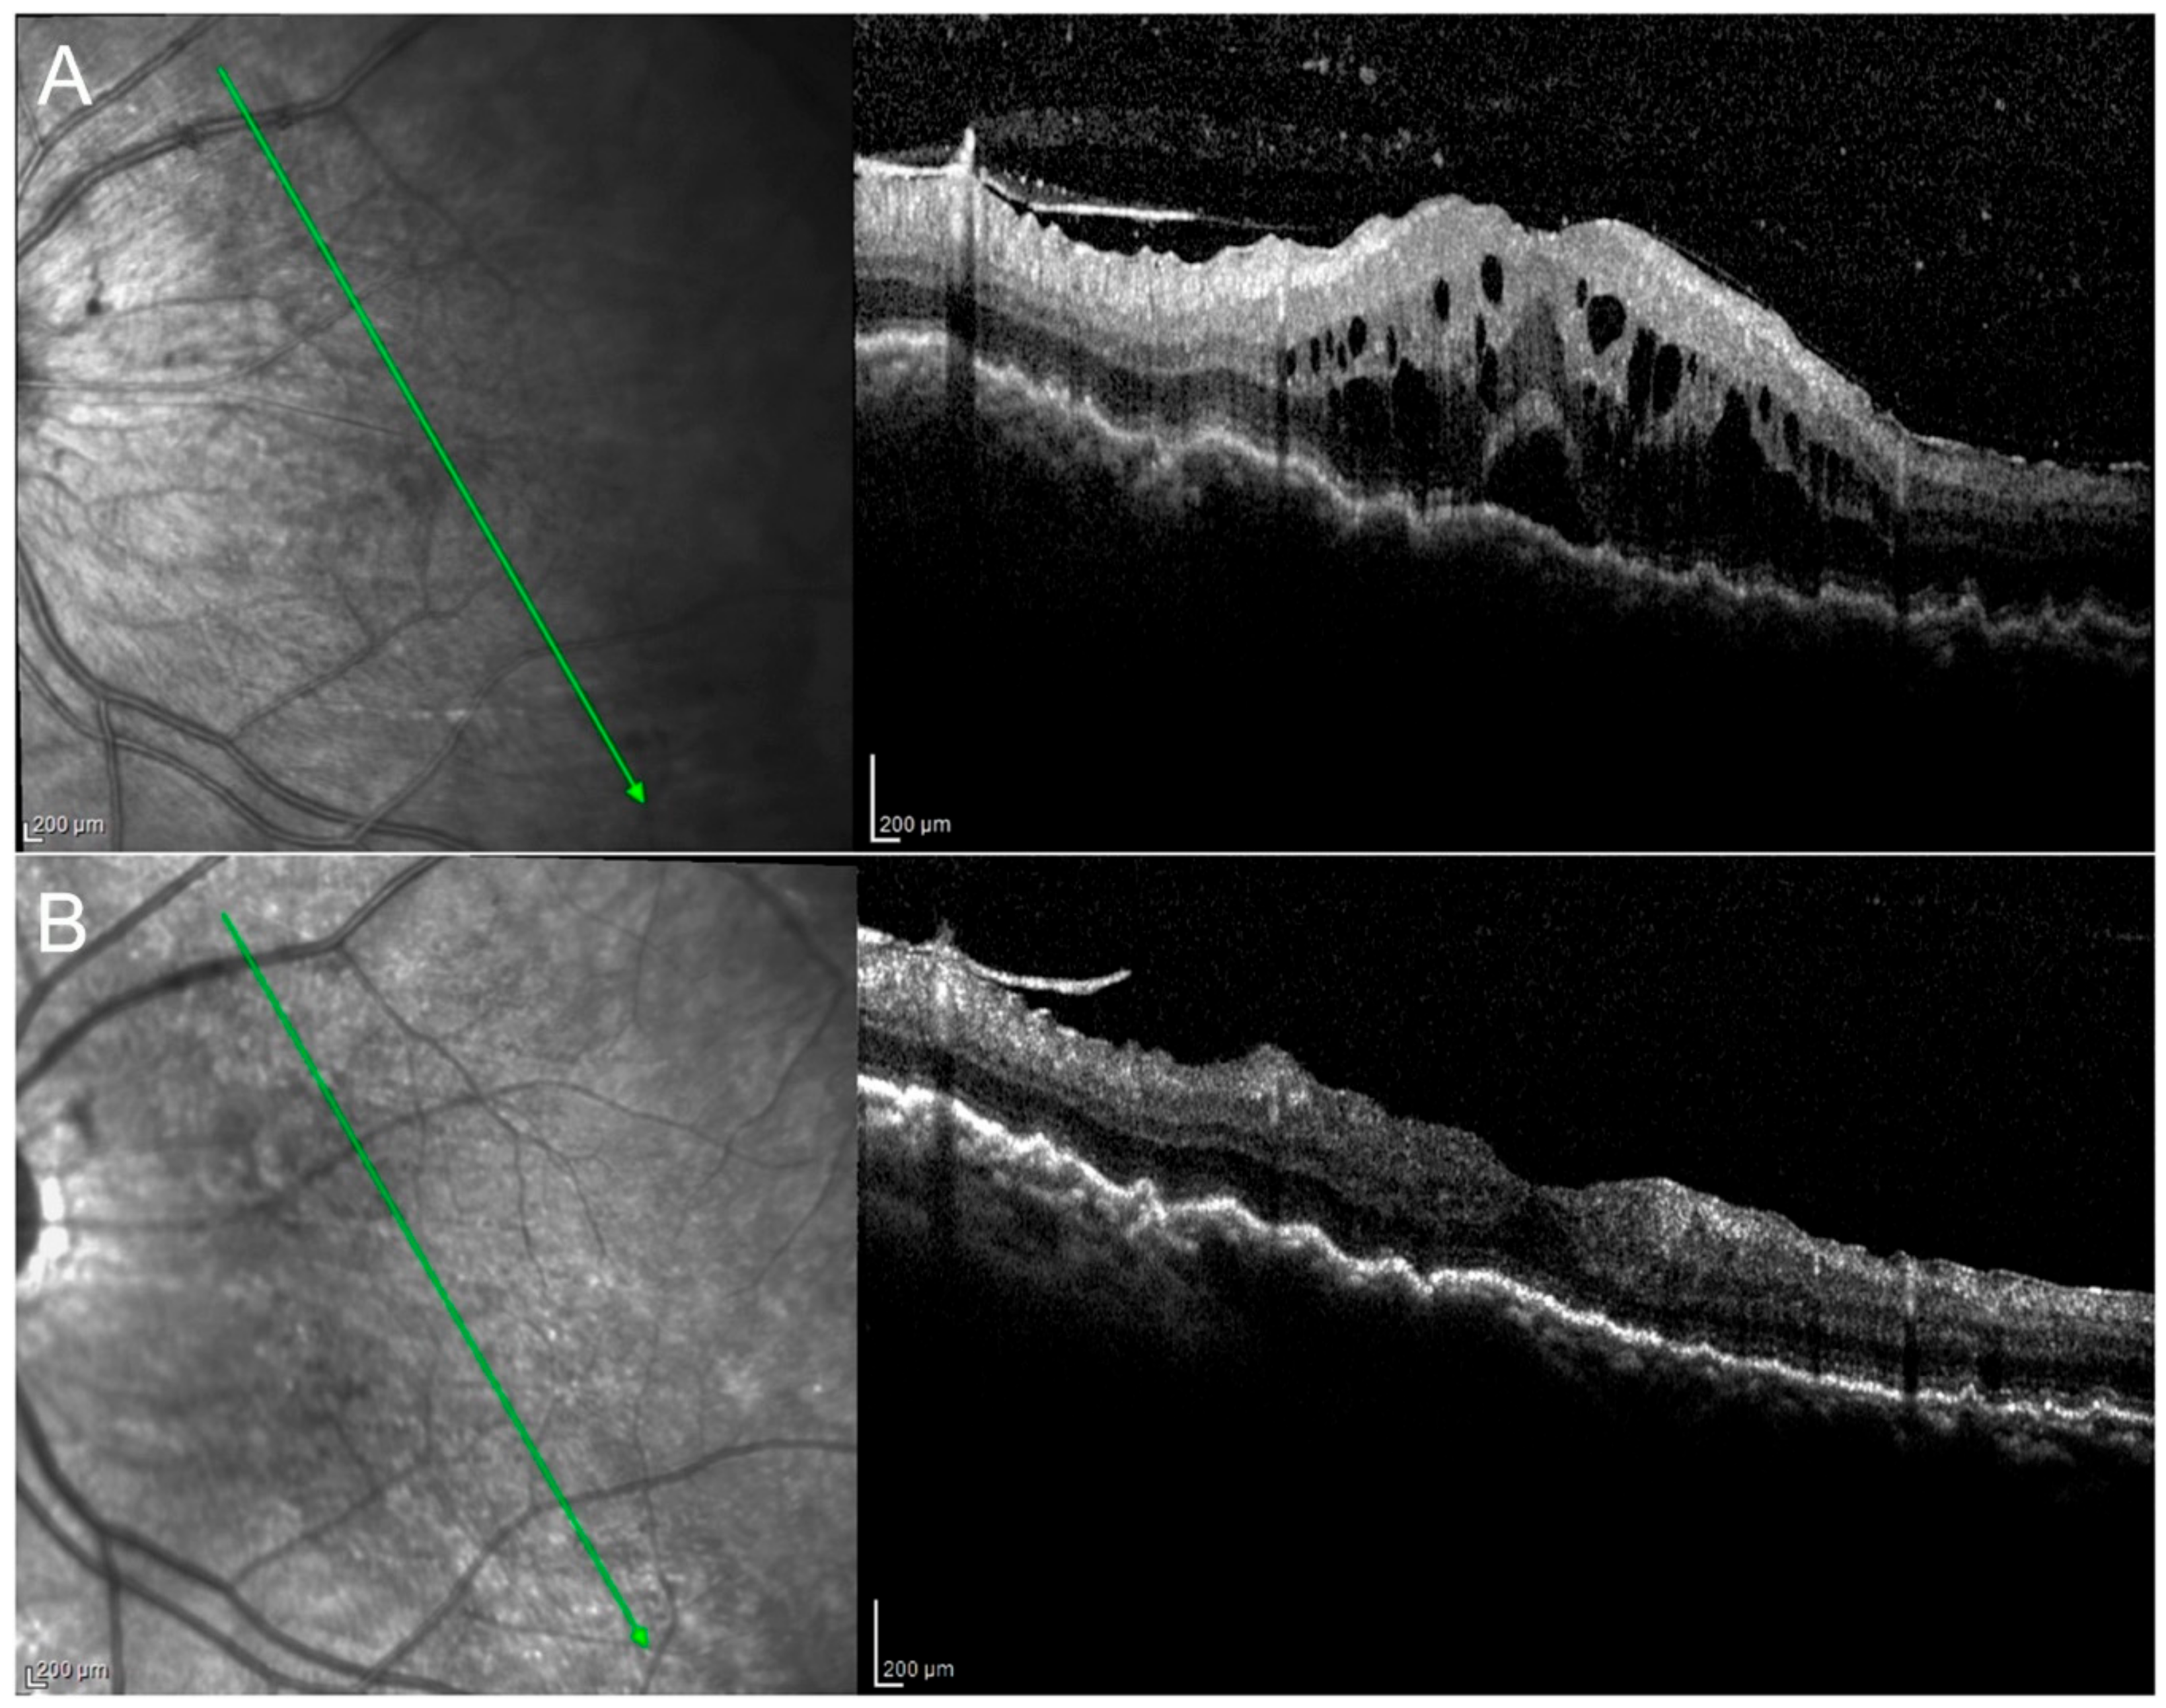

3.2. Changes in Macular Thickness and Visual Acuity

3.3. Changes in Choroidal Thickness